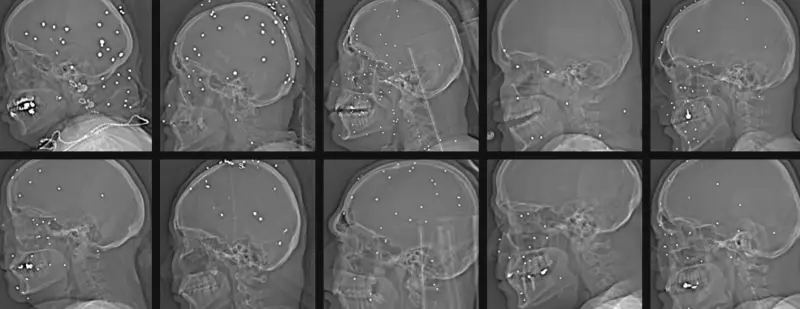

إحدى الحالات التي وثقتها الصور تعود لشابة في العشرينات تدعى أناهيتا، فقدت إحدى عينيها وربما كلتيهما بعد أن اخترقت عشرات الكرات المعدنية وجهها.

وأوضحوا أن استخدام "رصاص الطيور" من مسافات قريبة يحول كل طلقة إلى عشرات المقذوفات الصغيرة القادرة على تدمير الأنسجة الرخوة وإحداث نزيف داخلي خطير.